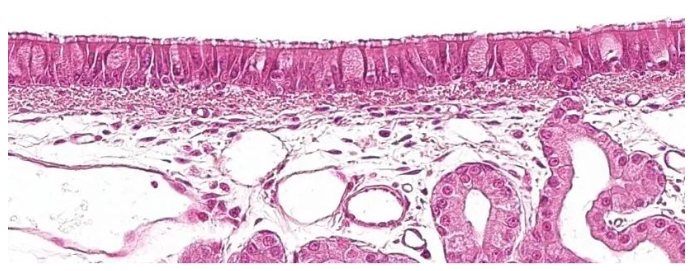

所有這些管狀結(jié)構(gòu)都內(nèi)襯有帶有杯狀細(xì)胞的纖毛假?gòu)?fù)層上皮(圖1),這是呼吸粘膜的主要防御系統(tǒng)之一,粘液纖毛系統(tǒng)。

圖1:帶有杯狀細(xì)胞的纖毛假?gòu)?fù)層上皮,是呼吸系統(tǒng)的特征